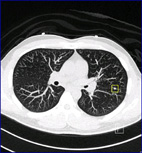

本圖片由本院影像醫學科提供,肺部電腦斷層掃描使用CAD功能所偵測到的影像(左圖),經放大後發現其為長3.85mm寬3.15mm的小結節(右圖),可協助各專科醫師進行進一步診斷。

近幾年來,電腦軟體不斷地更新與進步,使得電腦輔助檢測軟體CAD (Computer-Aided Detection)的應用愈來愈普遍,其功能是協助專業影像專科醫師在數位化電腦斷層胸腔影像中,發現、鑑定以及評估肺部病灶與結節,特別是發現直徑介於5-15 mm的小型結節,使肺部疾病可以提早發現,及早治療。